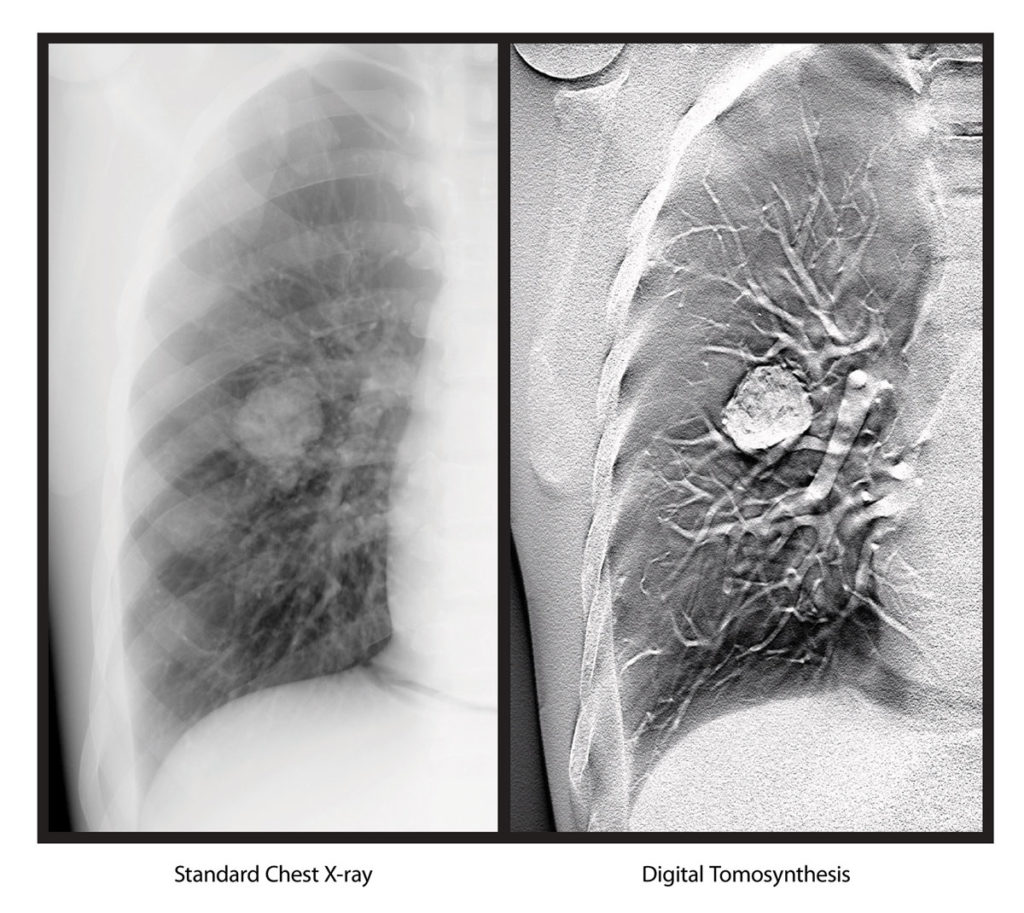

Digital Tomosynthesis uses a single sweep of X-ray exposures and streamlines operator workflow by separating the process of DT exposure acquisition from image volume formation. As a result, it can generate data from a series of low dose X-ray images of the same organ, taken at the same X-ray exposure, from different angles.

“The images captured by Digital Tomosynthesis technology offer greater depth and enhanced visualization,” said Sarah Verna, Worldwide Marketing Manager for Global X-ray Solutions at Carestream. “Doctors and radiologists will be able to perform scans quickly, providing valuable clinical information for further diagnosis while improving the workflow in an X-ray room.”

Digital Tomosynthesis, like a computed tomography (CT) scan, can produce cross-sectional images of an organ, allowing for increased visibility. This capability enhances the DRX-Evolution Plus in situations where physicians need quick answers.